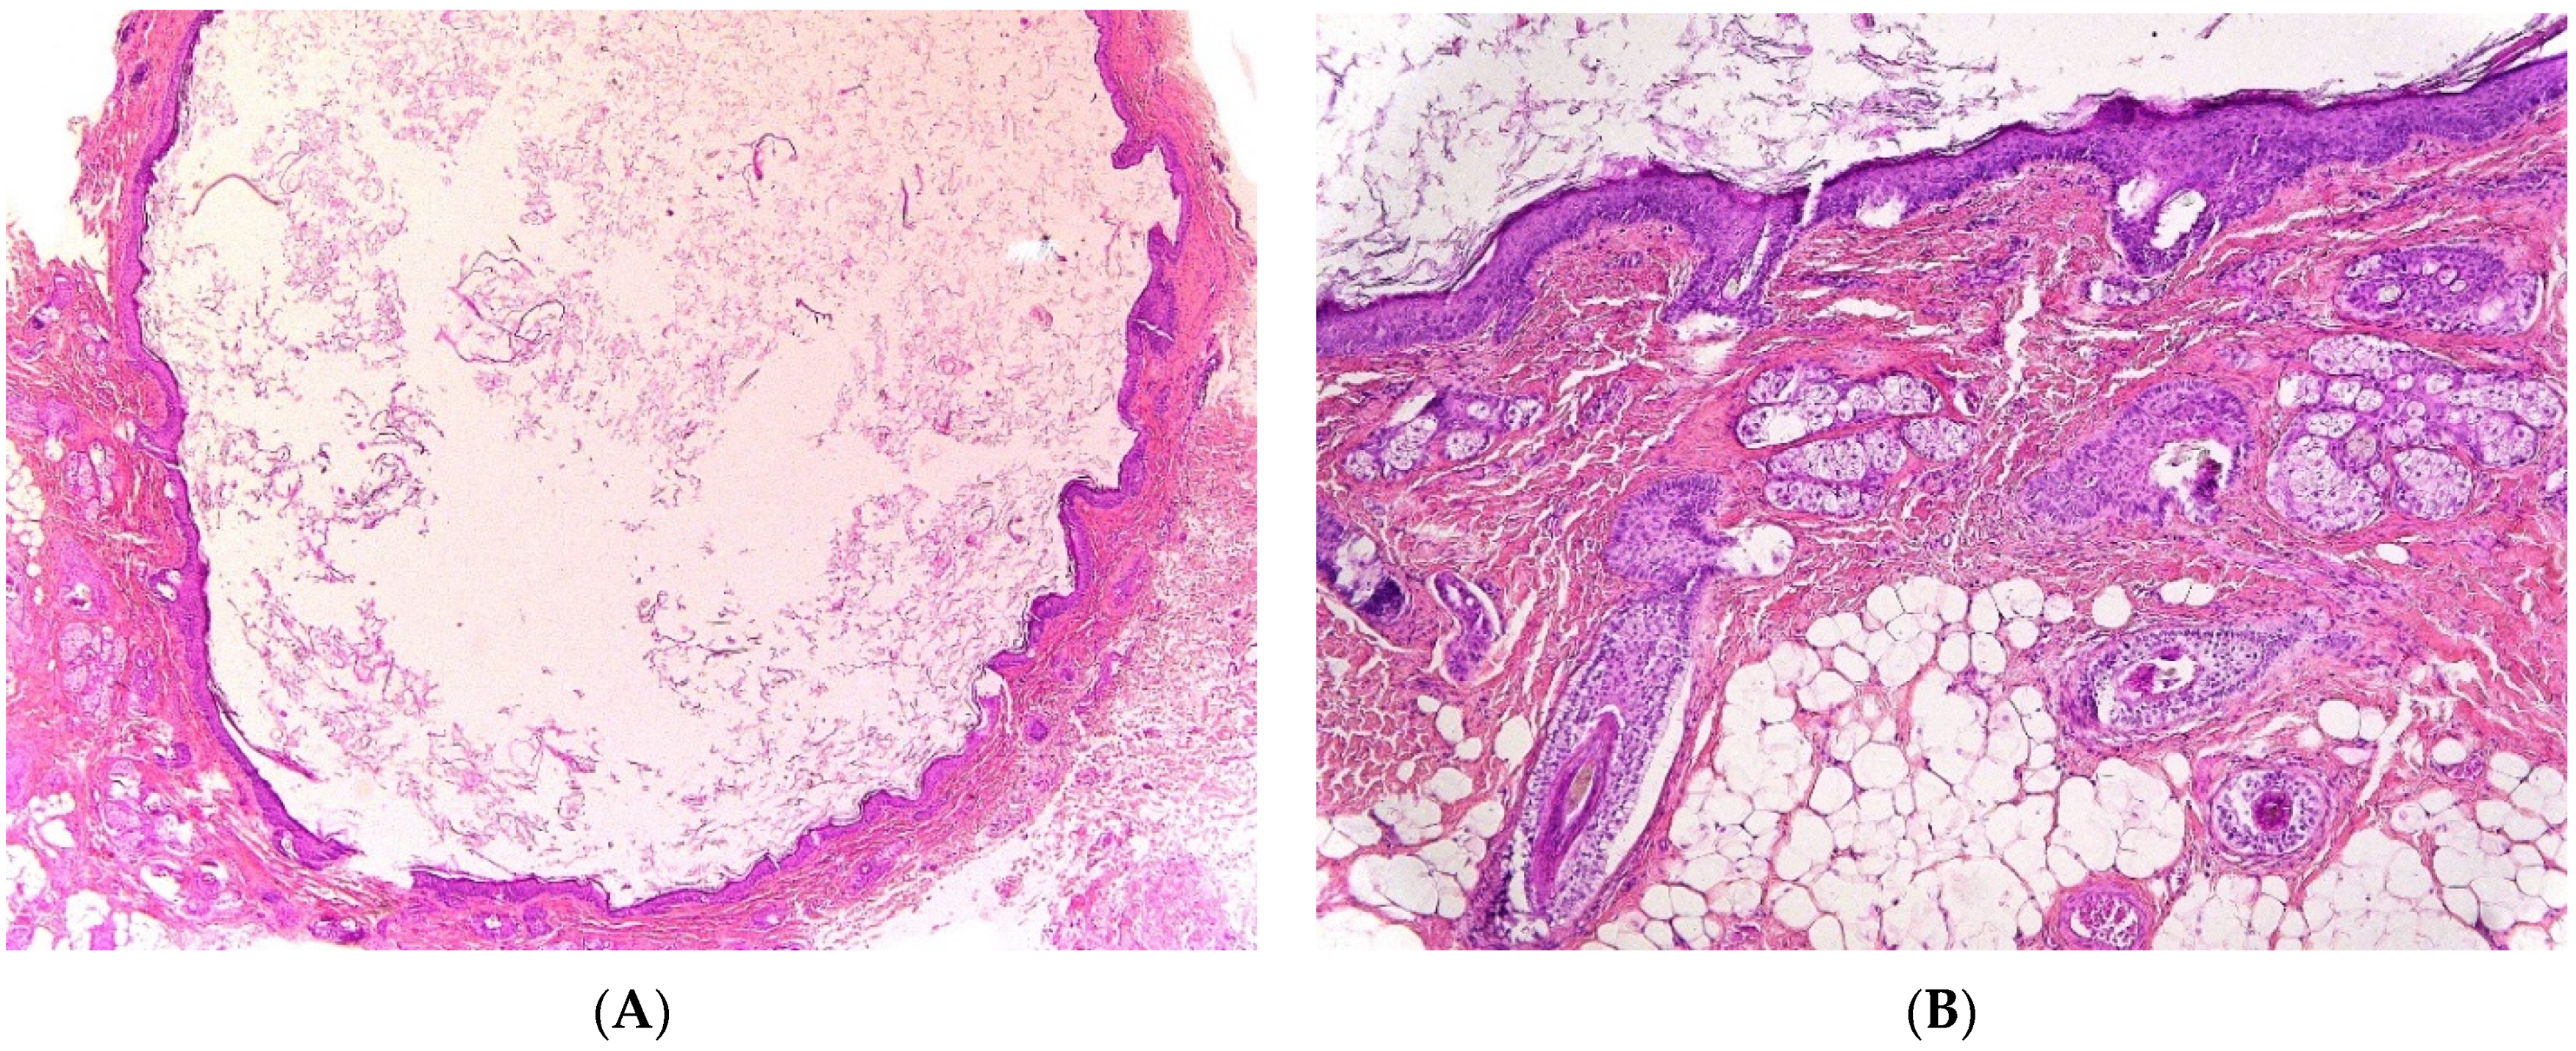

2.5.2. Histopathological Features

The cystic fluid may be clear, yellow, brown, green, or even purulent. The diagnosis is established by histologic demonstration of residual thymic tissue showing Hassall’s corpuscles and cortico-medullary differentiation (Figure 6A). The cyst wall lining may be spindle, cuboidal, or columnar, stratified or pseudostratified, ciliated or non-ciliated (Figure 6B). Cholesterol crystals, giant cells, histiocytes, inflammatory cells, and hemosiderin have also been described.

Figure 6.

Thymic cyst. (A), (H.E.S). Mature thymic tissue showing Hassall’s corpuscles (arrow) and cortico-medullary differentiation and arranged in lobules at the hypodermis. The overlying dermis is devoid of adnexa and replaced by scar-like fibrous tissue. (B), (H.E.S). Ductal-like structures (arrow) opening at the surface of the skin, lined by a columnar, pseudostratified epithelium (at the left, half part).

Congenital thymic cysts should be differentiated from multilocular thymic cyst, as the latter represents an acquired, multilocular, inflammatory lesion arising from cystic dilatation of the medullary duct and associated with autoimmune diseases, such as Sjogren’s syndrome and aplastic anemia. These acquired thymic cysts are lined by squamoid, cuboidal, columnar, micropapillary or mixed glandular epithelium, and can present with pseudo-epitheliomatous hyperplasia. Secondary inflammation is commonly found but no cartilage or smooth muscle can be identified [26].